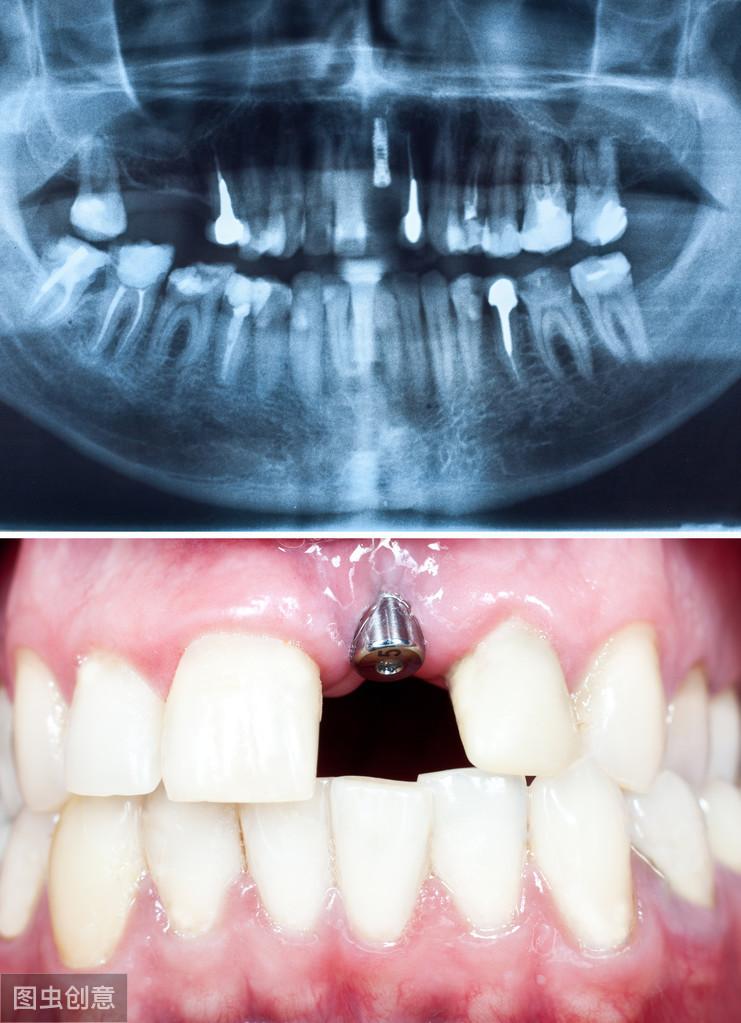

1. 口腔檢查:術(shù)前的口腔檢查很重要,如果有齲齒或其他牙周疾病,不提前進(jìn)行調(diào)節(jié)就可能會(huì)引起種植體感染,造成種植手術(shù)失敗,所以一旦口腔檢查時(shí)發(fā)現(xiàn)有口腔問題,應(yīng)先進(jìn)行調(diào)節(jié),尤其是齲齒等病灶牙;

如果沒有需要調(diào)節(jié)的口腔問題,就可以進(jìn)行牙槽骨估值檢測,因?yàn)榉N植體是直接植入牙槽骨的,所以骨質(zhì)的好壞也是決定能否接受牙齒種植的關(guān)鍵性因素。